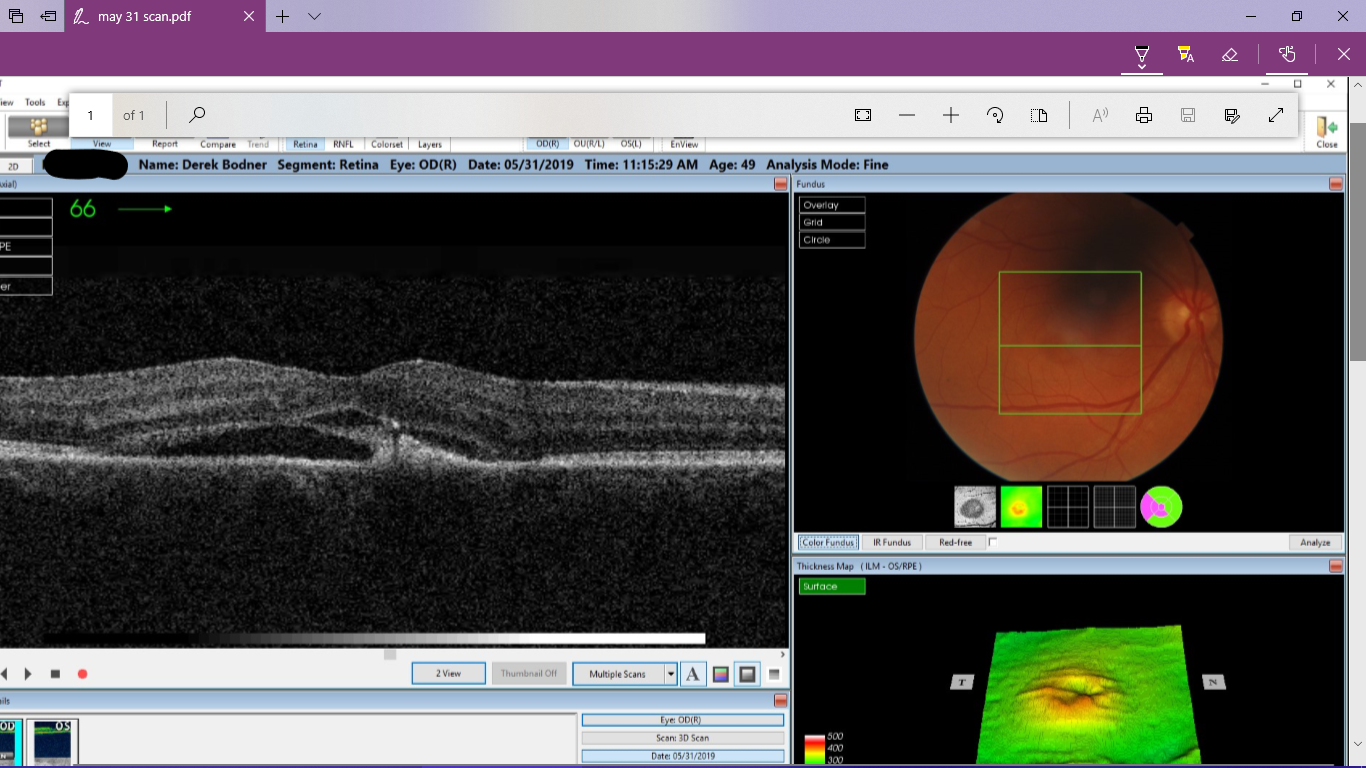

As with my last set of scans, Dr. Sarah Freiburger was kind enough to email me a copy of the scan I had done today so that I could share it with you. So I’m going to give her and Eye-Q Optometry a shout out. Check them out for your next eye exam, which I am urgiung everyone to get immediately.

The fluid is in fact draining from beneath the macula, but there is another pocket of fluid that has built up between the layers, the smaller bubble to the right of the larger one. Dr. Freiburger suspects this is the cause of the distortion.

A view of the surface relief also helps to explain things. My retina went from normal and smooth, to distorted yet still smooth, to distorted and resembling a crater. There is a small area with peaks and valleys on my macula, and until they all settle down, if they all return to normal that is, this is what I have to put up with.